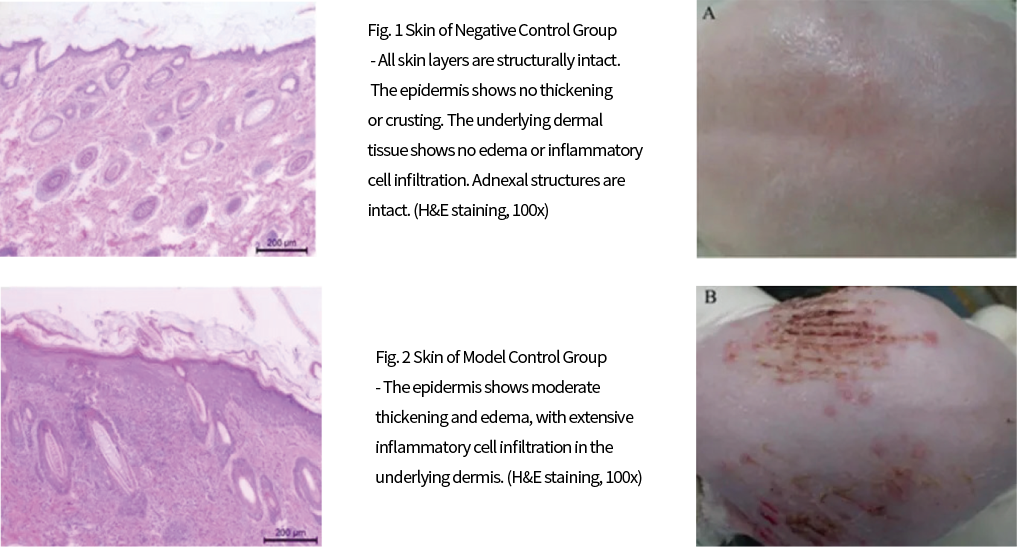

◆ Animal Models for Skin Diseases

Pressure Ulcer Model

A self-made pressure device (with good repeatability, simple and safe experimental operation and device) simulates pressure ulcer (decubitus ulcer) wounds of varying degrees in skin tissue by controlling pressure and time on a specific pressure area, forming pressure ulcers at different stages. It investigates wound healing and contraction rate, partially simulating the clinical characteristics of pressure ulcer occurrence.

Pressure Ulcer Modeling and Manifestations